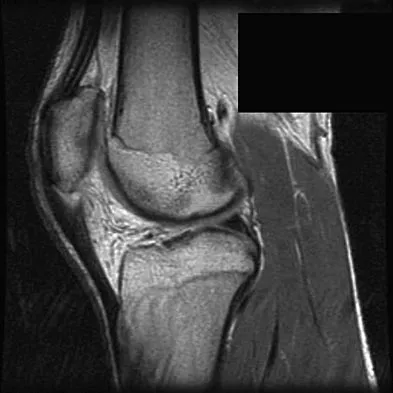

Figure 11 shows a consecutive sequence of MRI scans obtained in a 12-year-old boy who has had increasing lateral knee pain and catching for the past 6 months. Examination reveals pain localized to the lateral joint line. Range-of-motion testing reveals a 5-degree lack of full extension on the involved side. Plain radiographs and laboratory values are within normal limits. What is the most appropriate management?

Discoid menisci are rare causes of lateral knee pain in children. Various etiologies have been proposed, including failure of central absorption of the developing meniscus and hereditary transmission. Patients with discoid menisci have pain, clicking, and locking with a loss of active extension on range-of-motion testing. Classification of discoid menisci according to the Watanabe classification include complete, incomplete, and Wrisberg ligament type. The Wrisberg variant contains an abnormal posterior meniscal attachment. MRI is the diagnostic tool of choice, revealing a thick, flat meniscus generally seen in three consecutive MRI images. Symptomatic knees are often associated with a meniscal tear or degeneration and are managed with arthroscopic partial excision to a more normal shape (saucerization). Vandermeer RD, Cunningham FK: Arthroscopic treatment of the discoid lateral meniscus: Results of long-term follow-up. Arthroscopy 1989;5:101-109.

A 17-year-old basketball player and pole vaulter who has had anterior knee pain for the past 18 months now reports a recent inability to jump. Based on the MRI scan shown in Figure 11, management should consist of

The MRI scan reveals a partial patellar tendon rupture in conjunction with chronic patellar tendinitis. Mild and moderate patellar tendinitis may be treated nonsurgically with rest, stretching, strengthening, and anti-inflammatory drugs. Severe tendinopathy or extensor mechanism disruption is best treated surgically with tendon debridement and repair. Al-Duri ZA, Aichroth PM: Surgical aspects of patella tendonitis: Techniques and results. Am J Knee Surg 2001;14:43-50.